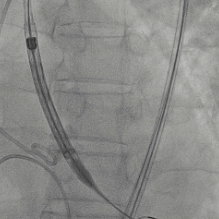

根部造影

最终造影